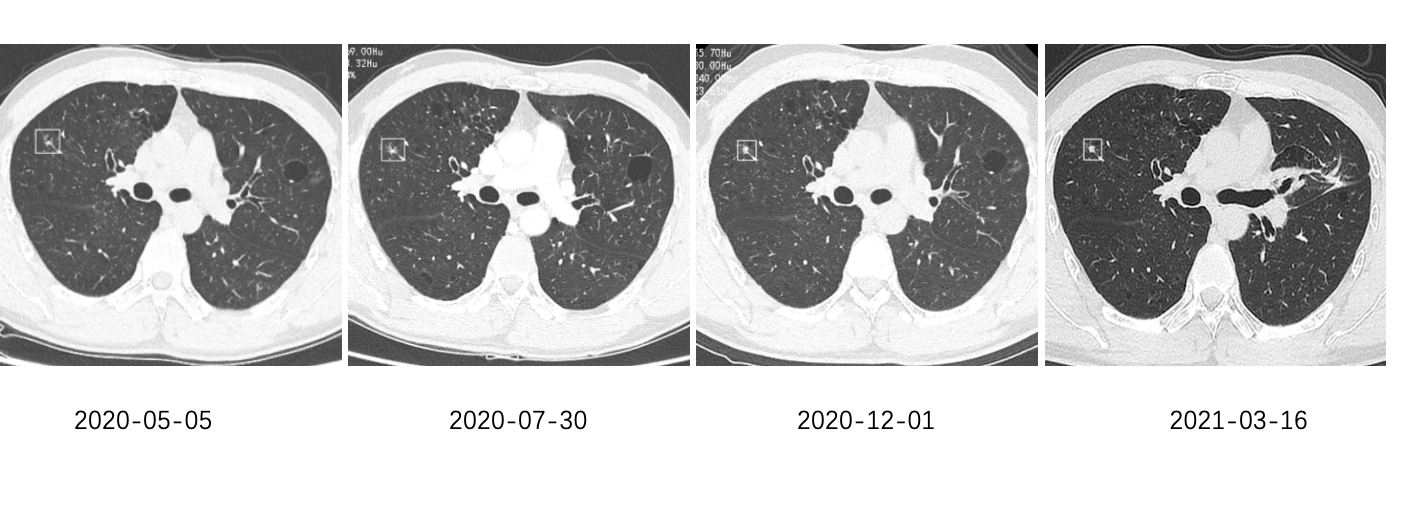

近日,我院呼吸与危重症医学科来了一个“老”病人。患者于2018年体检CT提示双肺多发结节、右肺中叶结节,大小约1.5*1.0cm,考虑恶性肿瘤的可能性大。去年,患者于全麻下行胸腔镜下肺肿瘤切除术(右),术后病理确诊为腺癌。经过4次化疗,并定期随访CT。去年5月份,从原先的6.89mm*5.3mm逐渐发展到了7.62mm*6.21mm。

经历波折,但是故事还远远没有结束。去年12月22日,患者行胸腔镜下左上肺肿瘤切除术,病理提示为“左上肺原位腺癌伴微浸润”。在随访过程中,发现患者右上肺的小结节的病灶密度增加了。这个病灶只有4.8*3.9mm,在未明确病灶是否是恶性的情况下,患者肺部已经经历过两次手术,接下来是否应该再次行手术?患者为此感到焦虑。对于患者来说,是个左右两难的大问题。带着这个困惑,患者来到我们医院。为进一步明确诊断,我们提出行磁导航气管镜检查,可以用最小的创伤来取得病理标本,避免再次手术带来的创伤和风险。